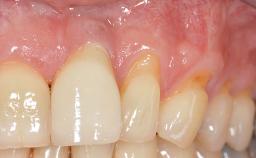

Paolo Casentini demonstrates that peri-implantitis can be successfully treated even at an advanced stage. He discusses a case in which the existing implants and prostheses were both retained while regenerating the defect and creating a band of keratinized tissue. A 69-year-old female patient was referred by her general dentist for evaluation of a recurrent infection at previously placed and restored implants in the posterior left mandible. The patient’s chief complaint was recurrent swelling and pain in the molar region of the left posterior mandible with discomfort during brushing in the same area. The patient reported receiving two implants (36 and 37) nine years earlier.